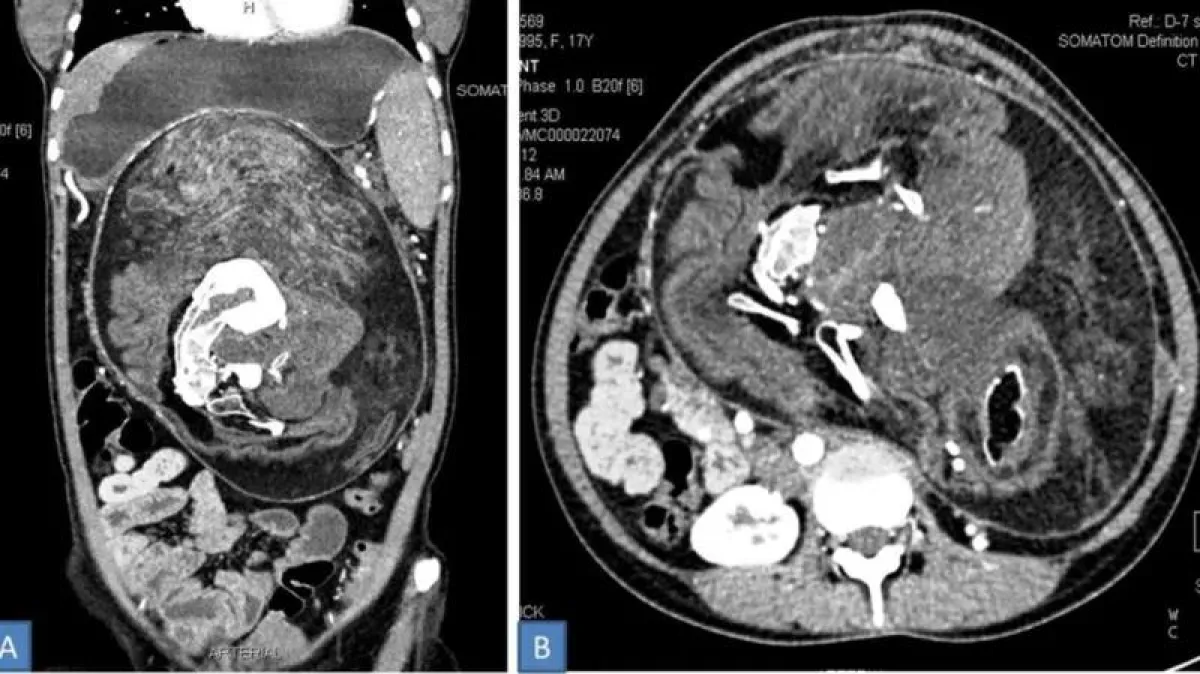

في الفحص المبدئي، كان الأطباء يشتبهون بوجود نوع من الورم، ولكن عندما قاموا بإجراء فحص CAT، وجدوا رواسب من الكالسيوم تبدو «على شكل فقرات وضلوع وعظام طويلة»، وفي النهاية تم اكتشاف الحقيقة ثم قام الأطباء بالعمل على إزالته.

ووفقًا للتقرير، فإن محتويات الورم تتألف من الشعر والعظام الناضجة وأجزاء الجسم الأخرى. وشملت هذه الأجزاء من الجسم «أسنان وهياكل متعددة تشبه براعم الأطراف، كما أن حجمها الهائل - 36 × 16 × 10 سم - يجعله الأكبر على الإطلاق فى حالة جنين البالع لجنين.. ولحسن الحظ، مع انتهاء الجراحة، تعافت المرأة ونالت الشفاء العاجل والهادئ ولا تزال في حالة جيدة.